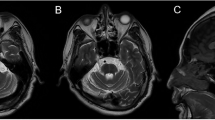

Patients 4 and 5 harbored missense variants in GRM1 (patient 4: c.3563A > C,p.K1188T; patient 5: c.1849T > C,p.Y617H). GRM1 (glutamate receptor metabotropic 1; MIM 604473) is associated with SCA44 (MIM 617691). The patients exhibited slowly progressive SCA with limb ataxia, saccadic eye movement, and dysarthria. Patient 4 presented with truncal ataxia, no-no head tremor, or cognitive decline (the mini-mental state examination: 15). Magnetic resonance imaging (MRI) of the patient’s head showed severe white matter lesions (Fig. 2A) and atrophy of the cerebellum and brainstem (Fig. 2A, B). Patient 5 exhibited spasticity and cerebellar atrophy (Fig. 2C, D).

Head images of the patients with GRM1 variants. A Axial fluid-attenuated inversion recovery images of Patient 4 show cerebellar and brainstem atrophy and white matter lesions in the periventricular and subcortical regions. B Sagittal T1-weighted image of Patient 5, showing cerebellar and brainstem atrophy. Axial (C) and sagittal (D) T1-weighted images of Patient 5 showed cerebellar and brainstem atrophy